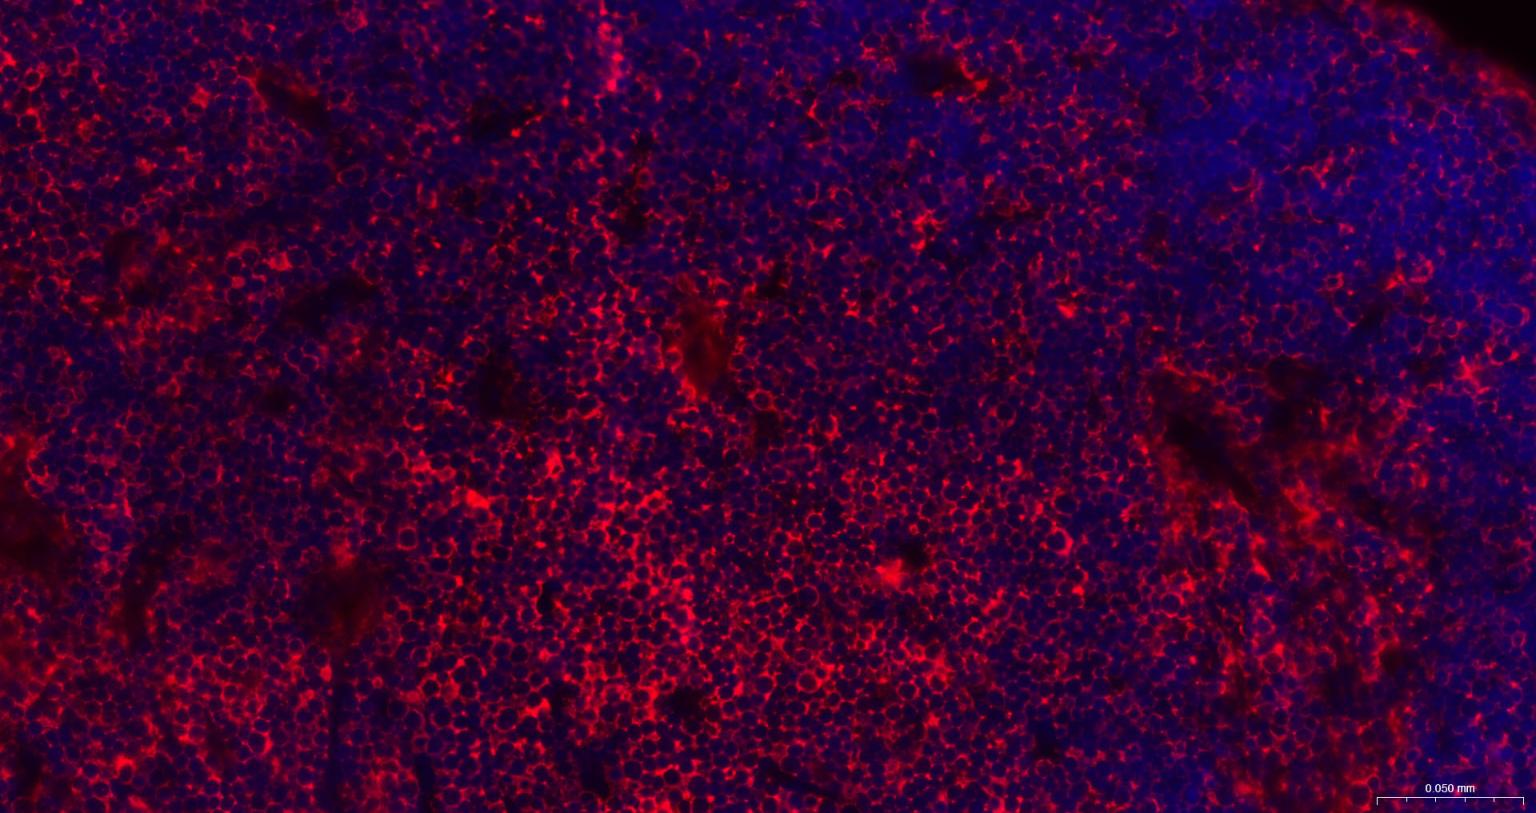

Paraformaldehyde-fixed, paraffin embedded Human Tonsil; Antigen retrieval by boiling in sodium citrate buffer (pH6.0) for 15 min; The section was incubated with STMN1 Monoclonal Antibody, Unconjugated (bsm-60306R) at 1:200 overnight at 4°C. Followed by conjugated Goat Anti-Rabbit IgG antibody (Red, bs-0295G-BF594), DAPI (blue, C02-04002) was used to stain the cell nuclei.